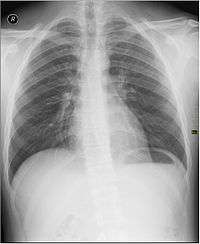

Radiographs (originally called roentgenographs, named after the discoverer of X-rays, Wilhelm Conrad Röntgen) are produced by transmitting X-rays through a patient. The X-rays are projected through the body onto a detector; an image is formed based on which rays pass through (and are detected) versus those that are absorbed or scattered in the patient (and thus are not detected). Röntgen discovered X-rays on November 8, 1895 and received the first Nobel Prize in Physics for their discovery in 1901.

In film-screen radiography, an X-ray tube generates a beam of X-rays, which is aimed at the patient. The X-rays that pass through the patient are filtered through a device called an grid or X-ray filter, to reduce scatter, and strike an undeveloped film, which is held tightly to a screen of light-emitting phosphors in a light-tight cassette. The film is then developed chemically and an image appears on the film. Film-screen radiography is being replaced by computed radiography (CR) but more recently by digital radiography (DR) and the EOS imaging.[1] In the two latest systems, the X-rays strike sensors that converts the signals generated into digital information, which is transmitted and converted into an image displayed on a computer screen. In digital radiography the sensors shape a plate, but in the EOS system, which is a slot-scanning system, a linear sensor vertically scans the patient.

Plain radiography was the only imaging modality available during the first 50 years of radiology. Due to its availability, speed, and lower costs compared to other modalities, radiography is often the first-line test of choice in radiologic diagnosis. Also despite the large amount of data in CT scans, MR scans and other digital-based imaging, there are many disease entities in which the classic diagnosis is obtained by plain radiographs. Examples include various types of arthritis and pneumonia, bone tumors (especially benign bone tumors), fractures, congenital skeletal anomalies, etc.